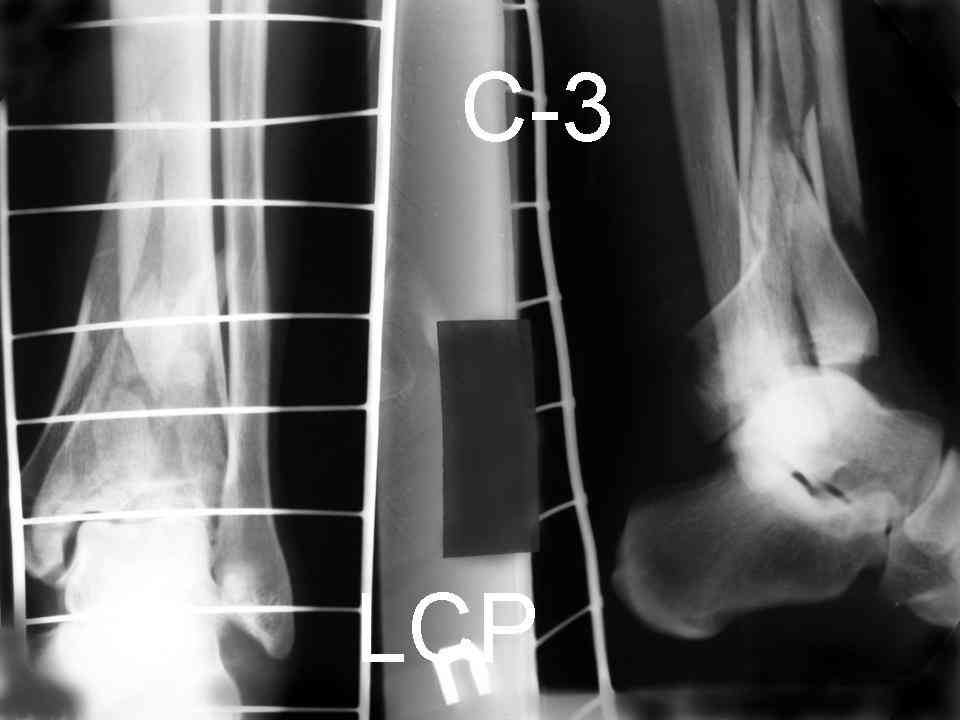

Re: Perelom N/3 kostei goleny

послал Дрягин В. 04 Январь 2007, 09:01

Послала ещё два снимка, если не пройдут, пошлю ещё. Дрягин. Если есть вопросы, готов ответить.